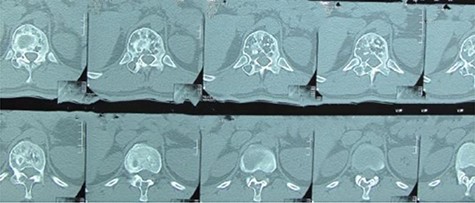

A 24-year-old male presented with acute low back pain with no prior traumatic events. Physical examination was unremarkable except for tenderness over the lower thoracic spine. The laboratory tests including complete blood count, renal function tests, alkaline phosphatase, aspartate aminotransferase, alanine aminotransferase, serum calcium, serum phosphorus and parathyroid hormone were all within normal limits. Initially, the patient was treated conservatively but the pain did not improve. Lumbar X-ray showed mild height loss and fracture of the superior endplate of T12 vertebra (Fig. 1). Computed tomography (CT) showed a multi-lobulated osteolytic lesion within the T12 body with extension to the right pedicle and transverse process (Fig. 2). Magnetic resonance imaging (MRI) revealed a well-defined lesion with low signal intensity on T1 and high signal intensity on T2 weighted images (Fig. 3). The bone scan showed a cold spot at the site of the lesion. The patient underwent surgery and excisional biopsy through the posterior approach. A large clear fluid-filled cavity was curetted and the cavity was filled with an autologous bone graft from iliac crest. Posterior spinal fusion was performed with instrumentation with pedicle screws from T10 to L2 and a mixture of autologous bone graft and allograft was used to achieve better fusion (Fig. 4). Pathology report confirmed the diagnosis of SBC and the patient received no further treatment (Fig. 5). The patient had no recurrence in 10-year follow up.

A 26-year-old male presented with pain over the lower lumbar area. Physical examination and laboratory tests were unremarkable with no neurologic deficit. X-ray and CT scans showed a lytic lesion with a sclerotic border in the right half of the body of the L5 vertebra (Figs 6 and 7). MRI showed a well-defined low signal lesion in T1 weighted images and high signal lesion in T2 weighted images (Fig. 8). The bone scan was negative. The patient underwent surgery and the lesion was extracted through the right pedicle and the remaining cavity was filled with an autologous bone graft from the iliac crest and right-side posterior fusion was done from L4 to L5 (Fig. 9). The pathology report was consistent with SBC. The patient had no recurrence seven years after surgery.